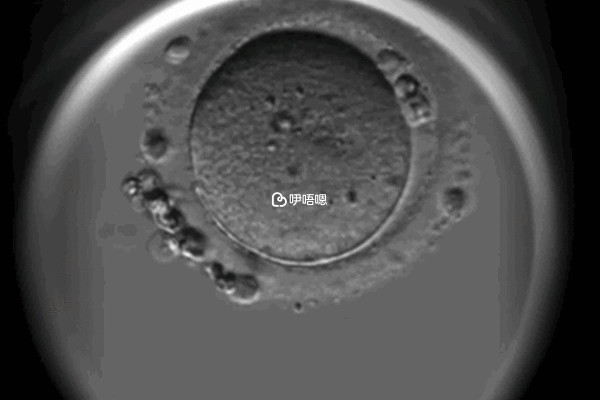

人工週期降調28天后返院內膜2C最快多久能移植凍胚,要根據患者的實際情況來決定。正常情況下,降調28天后患者身體達到移植標準,在2-3周左右就可移植凍胚,但由於個體差異,具體凍胚的移植時間也是因人而異的。建議患者可以諮詢自己的主治醫生,嚴格遵循醫囑,選擇適合自己的時間去移植凍胚,從而提高試管嬰兒的成功率。

降調人工週期移植凍胚整個用藥流程大約需要持續一個月左右的時間,降調人工週期包括13天左右的雌激素補充、十天左右的凍囊胚培養和冷凍、10天左右的內膜準備,當然這些流程走完之後也不一定能夠移植,還需要看患者的身體條件是否滿足,具體如下: